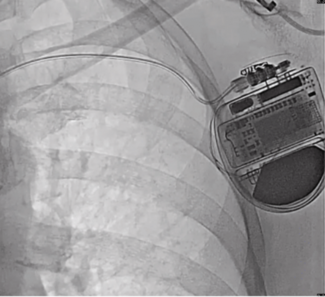

Dr Samira Teeri and colleagues share a case highlighting the management of transvenous lead-related complications in a patient with a dual-chamber pacemaker through the use of leadless pacemaker technology.